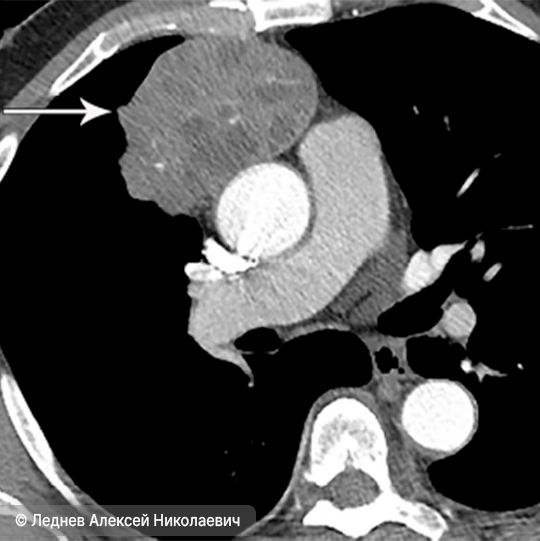

- Компьютерную томографию. Это наиболее точное и обязательное исследование, которое даёт объёмное изображение грудной полости. Оно помогает определить размер опухоли, её форму, расположение и давление на соседние органы.

Тимома на снимке магнитно-резонансной томографии (показана стрелкой)